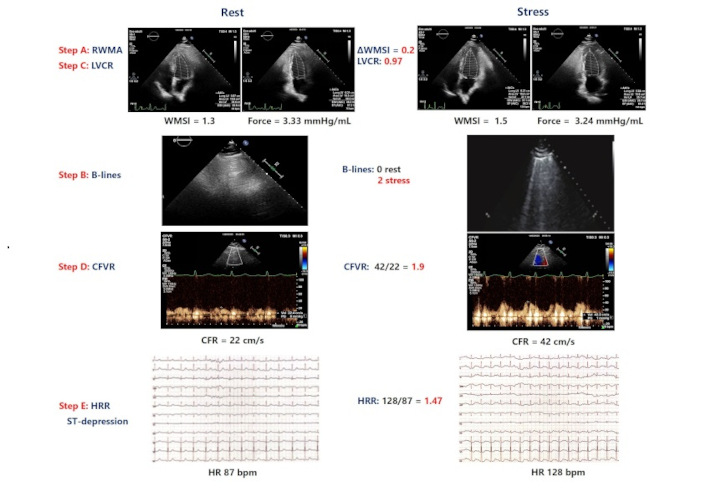

Central illustration. An example of a patient with positive ABCDE dipyridamole stress: induced ST-segment depression, new wall motion abnormalities (WMSI, step A positive), B lines at peak stress (step B positive), abnormal left ventricular contractile reserve (LVCR, step C positive) reduced coronary flow velocity reserve (CFVR, step D positive). RWMA: regional wall motion abnormality; LVCR: left ventricular contractile reserve; CFVR: coronary flow velocity reserve; CFR: coronary flow reserve; HRR: heart rate reserve; AWMSI: average wall motion score index; WMSI: wall motion score index; HR: heart rate